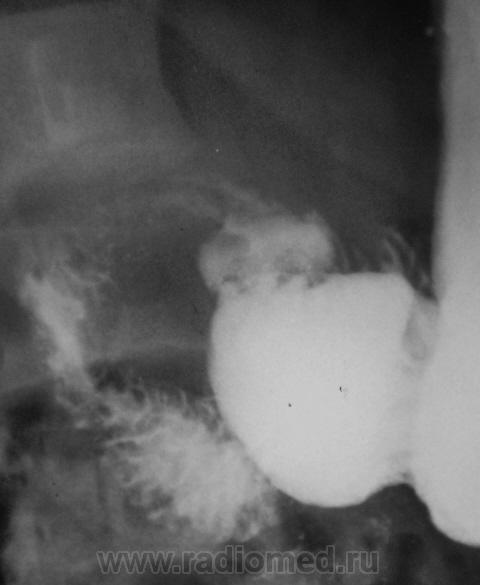

Вообще довольно часто встречающаяся ситуация с военкоматом, когда эндоскосписты, что-то нашли, а "рентген" не нашел. Но в данном случае наоборот - эндоскописты кроме "гастритика" ничего не нашли, рентгенологи дали заключение о наличии язвенной болезни 12-ти перстной кишки. Что делать терапевту, который будет писать акт, что делать эксперту, который будет выносить решение?

Принесли вот такие сгимки, спрашивают мнение.

"Язва" луковицы есть.....и на "рельефе" и на "конутре" "ниша" просматривается. Может у кого то будет другое мнение. послушаем.

На всей серии снимков формально - ниша в луковице. Однако на всех же снимках она хорошо заполнена, нет раздражения - главного косвенного признака... Возможно это в гипотонии? А в заключение - рубцовая деформация...